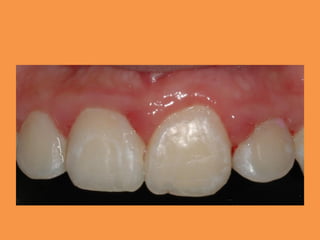

Figure 6; Intraoral view showing the

complete alignment of 11

Figure 6; Intraoralview showing the complete alignment of 11

• 32.